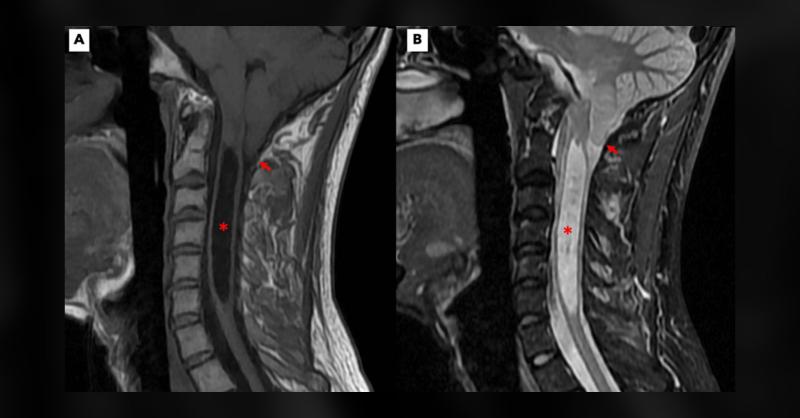

A 33-year-old male presented with a two-year history of gradually worsening proximal weakness in both upper extremities (1). He had difficulty with overhead activities but no issues with manual tasks involving his hands. Neurologic examination revealed bilateral scapular winging (serratus anterior type), mild weakness in the bilateral triceps and s